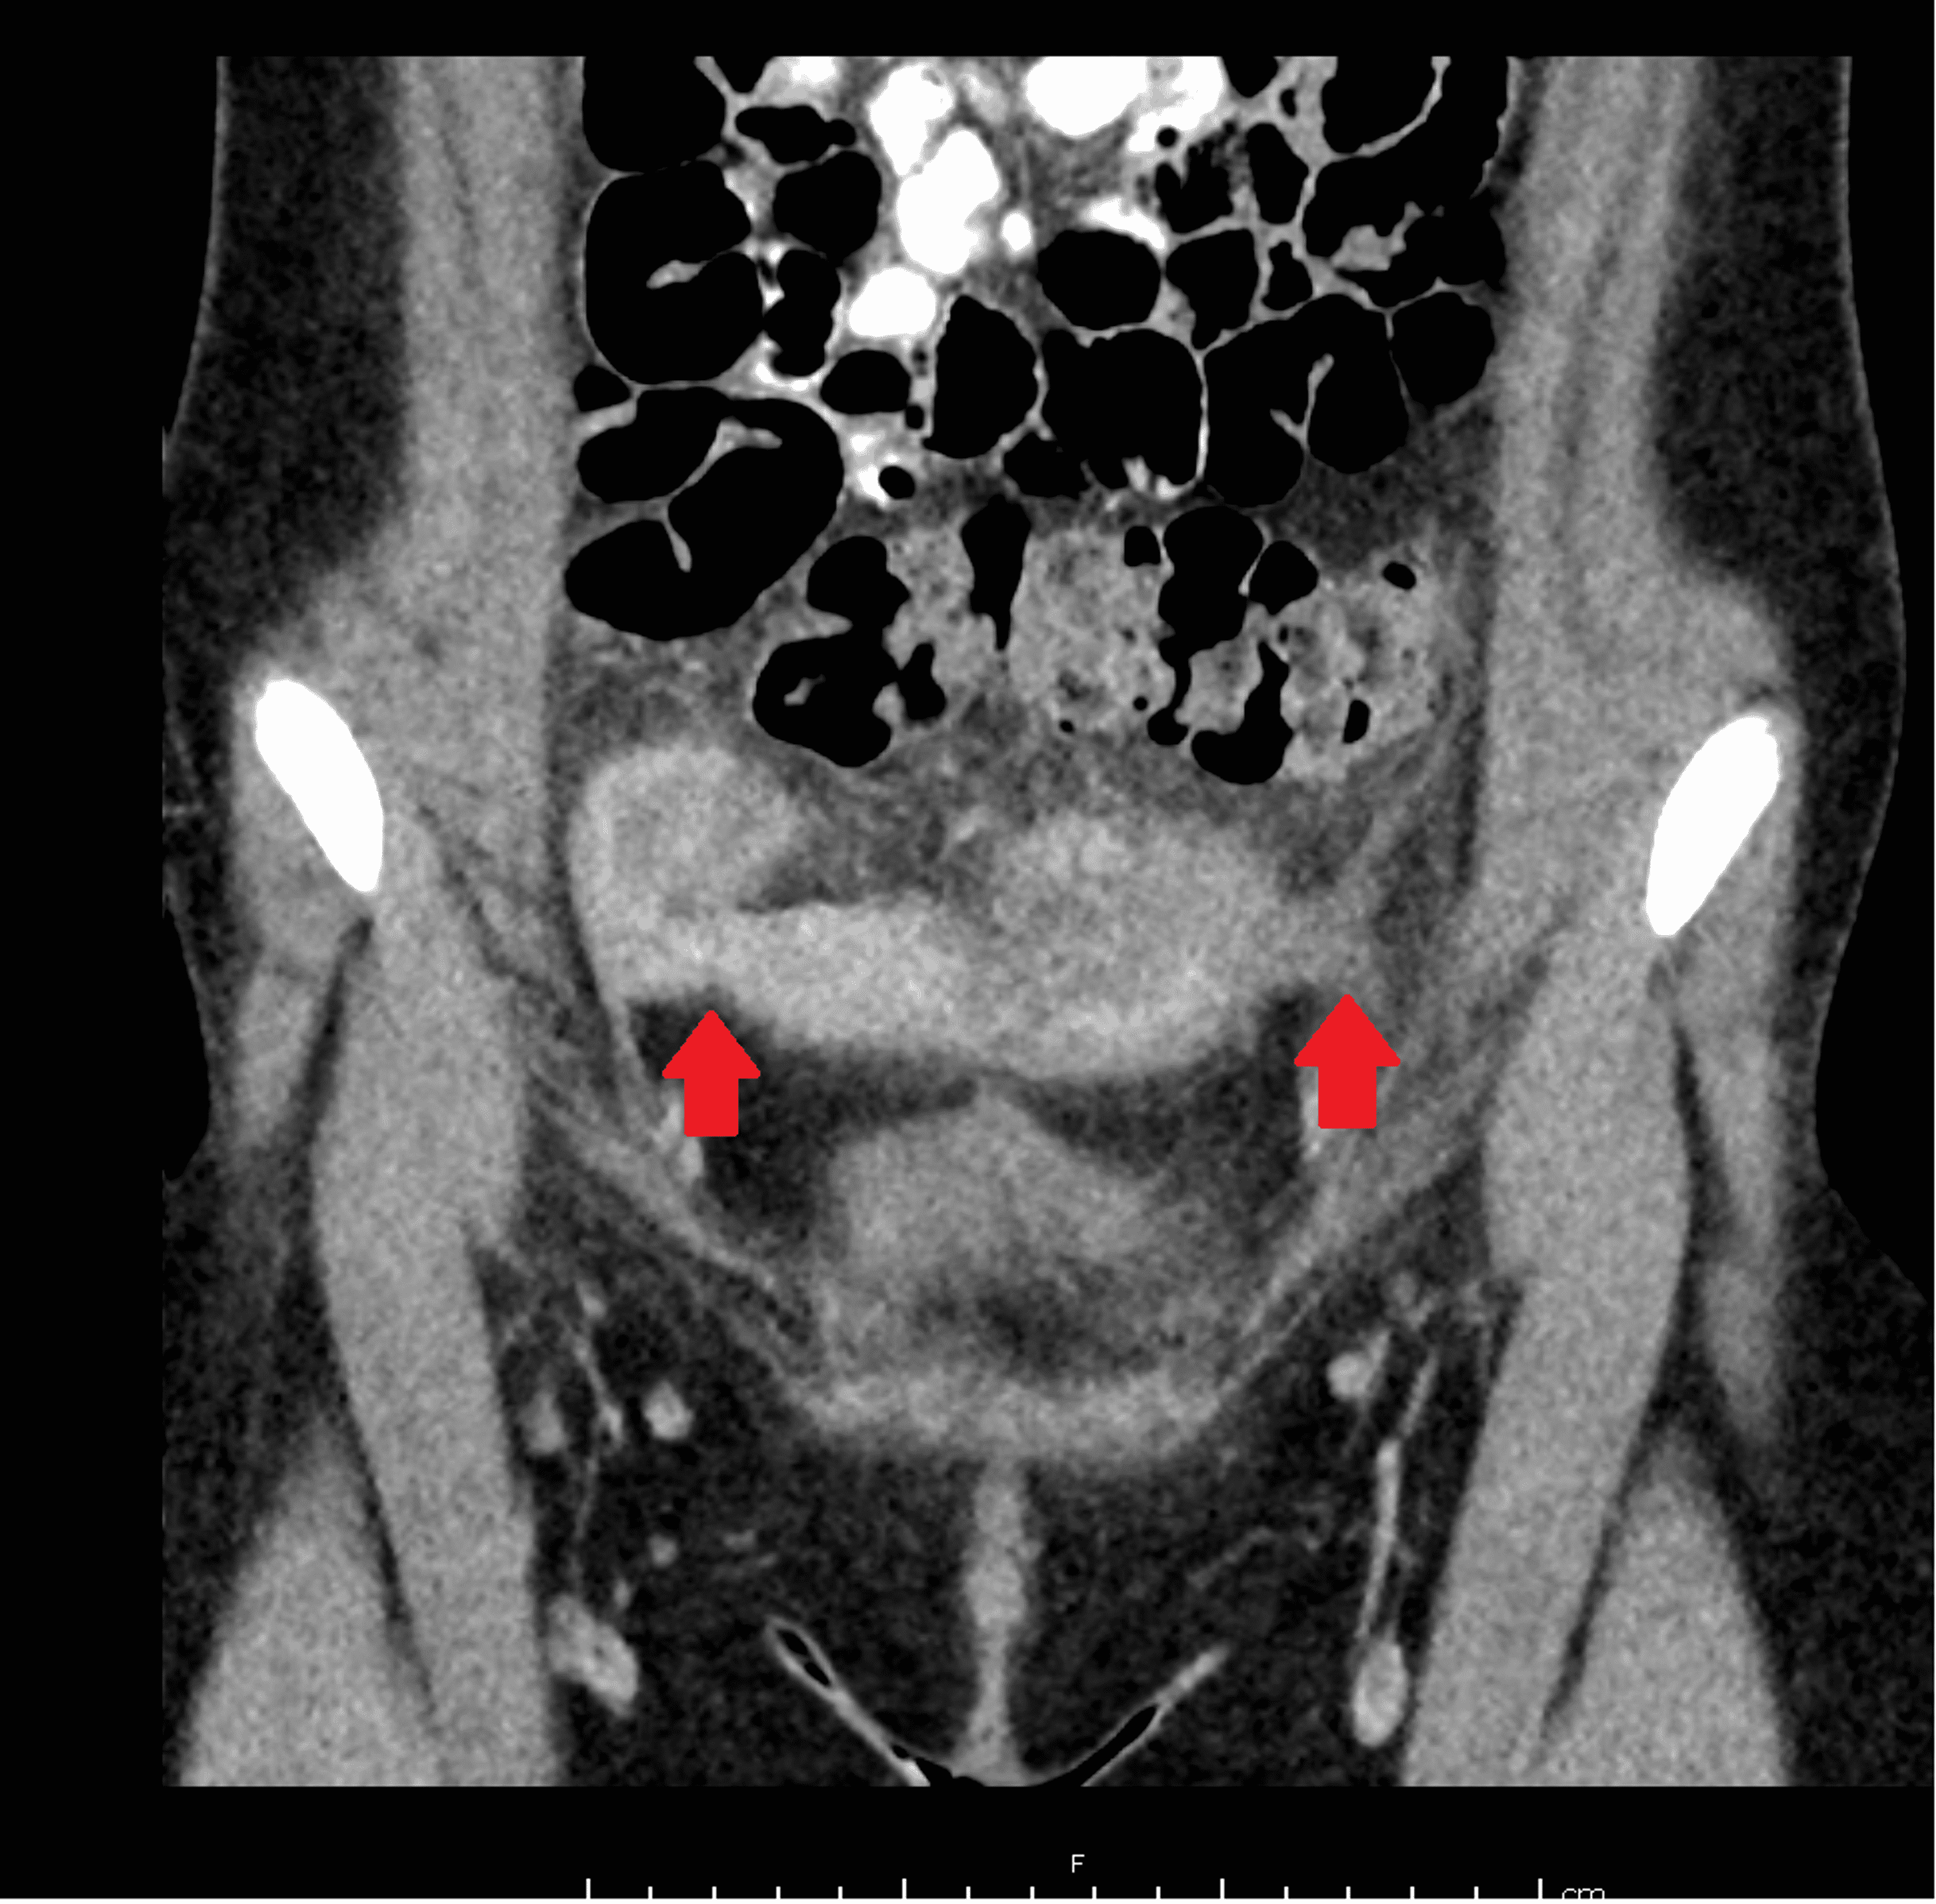

Cureus The Role of a Spinning Top Urethra in the Development of What Is Spinning Top Urethra 2b) , characterized by dilation of the. the more common outlet dysfunction is the spinning top urethra. spinning top urethra (stu) is a term used to describe a widened posterior urethra seen mainly in girls. an anteroposterior image from the voiding phase shows focal dilatation of the posterior urethra between the internal. It is seen on vcug. What Is Spinning Top Urethra.